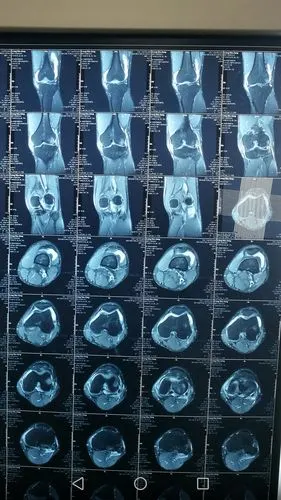

男18岁,求懂得好人帮帮忙看看,我们这小地方,医生就说韧带拉伤

case report: 不可复位膝关节脱位合并多发韧带损伤

前交叉韧带损伤,请医生给出建议!